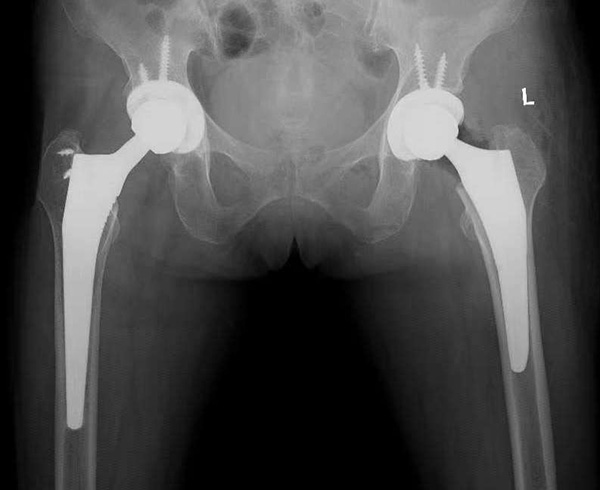

安放假体后校验显示左髋较术前长12mm,较对侧长2mm。肢体长度差异达到毫米级。

术后复查床旁骨盆X光片显示左髋假体位置:髋臼外展角、前倾角、假体偏心距及肢体长度均与术前计划一致。